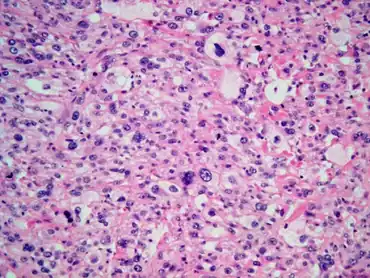

Malignant fibrous histiocytoma of urinary bladder as a post-radiation secondary cancer-Highly pleomorphic neoplastic cells with clear eosinophilic cytoplasm